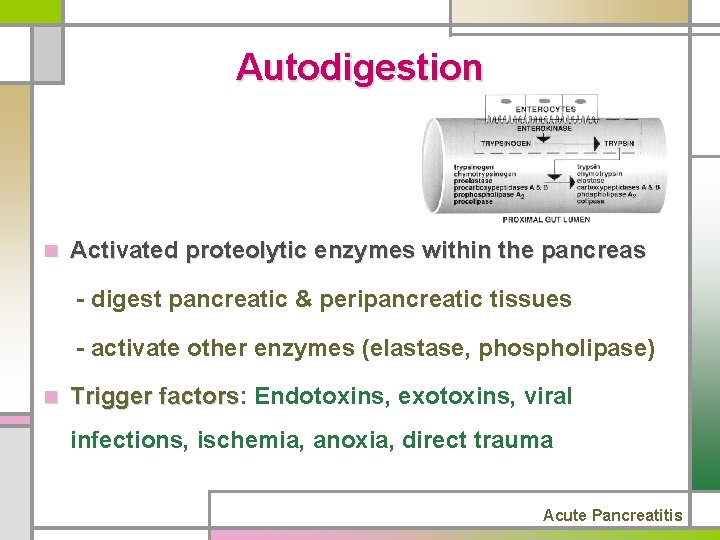

Autodigestion n Activated proteolytic enzymes within the pancreas - digest pancreatic & peripancreatic tissues - activate other enzymes (elastase, phospholipase) n Trigger factors: factors Endotoxins, exotoxins, viral infections, ischemia, anoxia, direct trauma Acute Pancreatitis